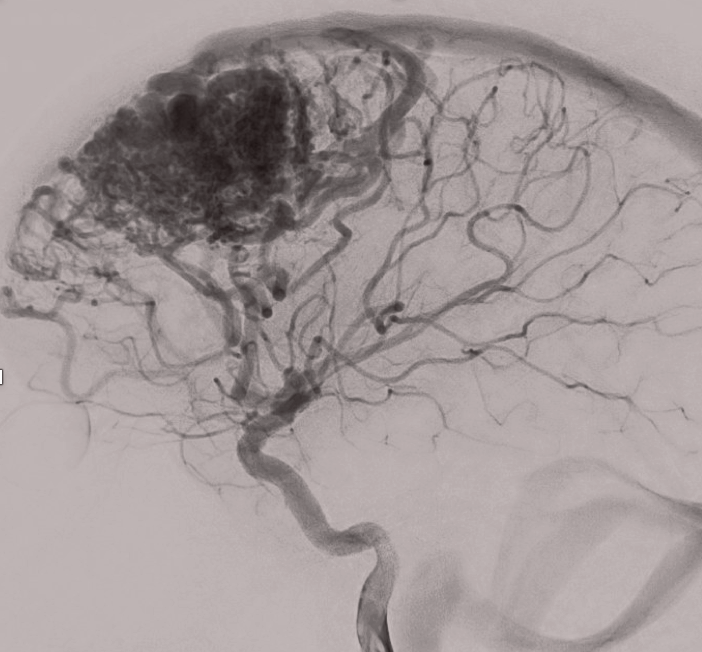

The Río Hortega Neurovascular Unit is a group of professionals with experience in the diagnosis and treatment of neurovascular pathology by open and endovascular techniques.

We have built a multidisciplinary team focused on the diagnosis and treatment of cerebral and spinal vascular disease that has extensive experience and a highly qualified team of professionals.

- Multidisciplinary vision Multimodal therapeutic approach directed to the individual patient Updating, constant improvement and quality control